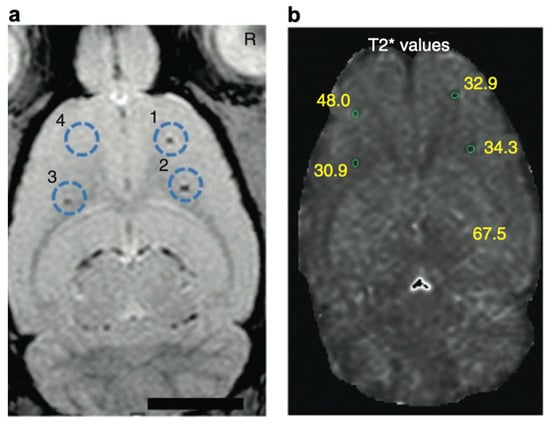

- Thu, M.S.; Bryant, L.H.; Coppola, T.; Jordan, E.K.; Budde, M.D.; Lewis, B.K.; Chaudhry, A.; Ren, J.; Varma, N.R.S.; Arbab, A.S.; et al. Self-assembling nanocomplexes by combining ferumoxytol, heparin and protamine for cell tracking by magnetic resonance imaging. Nat. Med. 2012, 18, 463–467. [Google Scholar] [CrossRef] [PubMed]

- Yin, Y.; Zhou, X.; Guan, X.; Liu, Y.; Jiang, C.; Liu, J. In vivo tracking of human adipose-derived stem cells labeled with ferumoxytol in rats with middle cerebral artery occlusion by magnetic resonance imaging. Neural Regen. Res. 2015, 10, 909–915. [Google Scholar]

- Bryant, L.H.; Kim, S.J.; Hobson, M.; Milo, B.; Kovacs, Z.I.; Jikaria, N.; Lewis, B.K.; Aronova, M.A.; Sousa, A.A.; Zhang, G.; et al. Physicochemical characterization of ferumoxytol, heparin and protamine nanocomplexes for improved magnetic labeling of stem cells. Nanomed. Nanotechnol. Biol. Med. 2017, 13, 503–513. [Google Scholar] [CrossRef] [PubMed][Green Version]

- Zhao, J.; Guan, X.; Liu, Y.; Piao, H.; Liu, R.; Zhou, X.; Sun, B.; Du, Y.; Liu, J. Potential role of tracing stem cell transplantation and effects on the immune cell function of ferumoxytol combining with heparin and protamine in vivo/in vitro. Cell Biol. Int. 2017, 41, 423–432. [Google Scholar] [CrossRef]